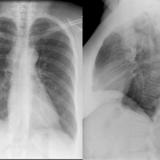

Situs inversus

Date: 10/22/2010

Views: 4553